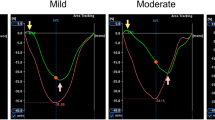

Restrictive mitral valve annuloplasty is currently recommended in surgical treatment of patients with IMR. However, IMR often persists or recurs after this procedure. It has been indicated that the posterior mitral leaflet angle ≥45° may be an accurate predictor of persistent or recurrent mitral regurgitation. Moreover, the posterior mitral leaflet angle ≥45° can be associated with a poor clinical outcome over a 3-year follow up [3].

Anterior and posterior mitral leaflet angles were determined by TTE and CMR in the 4-chamber view in mid-systole. The AML and PML angles were measured directly between the mitral leaflets and mitral annulus plane [3] as shown in Fig. 1.

There is a great interest in identifying new parameters of IMR severity. Kwan and colleagues [19] indicated the posterior leaflet angle of >47o as the cut-off value discriminating between significant (≥moderate) and non-significant IMR (sensitivity of 96% and specificity of 84%). Magne and co-workers [3] suggested that posterior leaflet angle ≥45° was related to a poor 3-years outcome in patients after mitral valve repair due to IMR. However, not only severe but also mild IMR is associated with an adverse prognosis due to the an additional hemodynamic load on the post-infarcted ventricle [20].

Recurrent IMR despite surgical annuloplasty is related to leaflet tethering by progressive left ventricular remodeling [30–33]. Among the pre-operative echocardiographic parameters, obtained by transthoracic approach, the most important in predicting persistent or recurrent MR after annuloplasty are tenting area 2.5 cm2, coaptation height 1.0 cm, central jet of MR, complex regurgitant jets, restrictive diastolic filling profile, severe enlargement of the left ventricle and posterior mitral leaflet angle value ≥45° [21, 34]. In a study of 51 patients subjected to mitral valve repair, those with posterior mitral leaflet angle value ≥45° had significantly lower 3-year event-free survival (22 ± 17% vs. 76 ± 12%, P < 0.001) [3].

We showed that the posterior mitral leaflet angle value highly correlated with regurgitant volume and tenting area (r = 0.90, r = 0.90, respectively). However, our findings also suggest that it may be important to evaluate the anterior mitral leaflet angle, especially in the group of patients with a more severe MR (RV > 30 ml). In those patients, we found a strong correlation between the anterior mitral leaflet angle and regurgitant volume or tenting area (r = 0.97, r = 0.82 respectively). Thus our current findings and those of Magne and colleagues [3] indicate that the consideration of the anterior leaflet angle in combination with the other indices of mitral valve morphology may be useful to guide the operative strategy. In our study group, the five patients (11.9%) with the posterior mitral leaflet angle value >45° were referred to mitral valve replacement with chordal sparing.